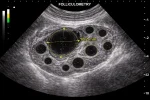

- УЗИ органов малого таза;

- УЗИ плода при беременности (включая 3D/4D).